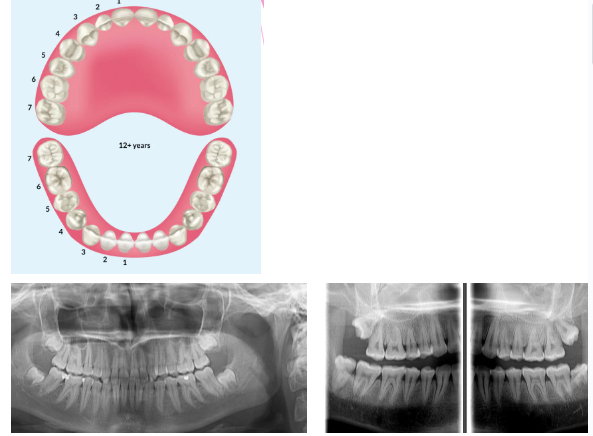

Mixed dentition stage

knowt flashcard image

Permanent dentition stage

Tooth eruption sequence